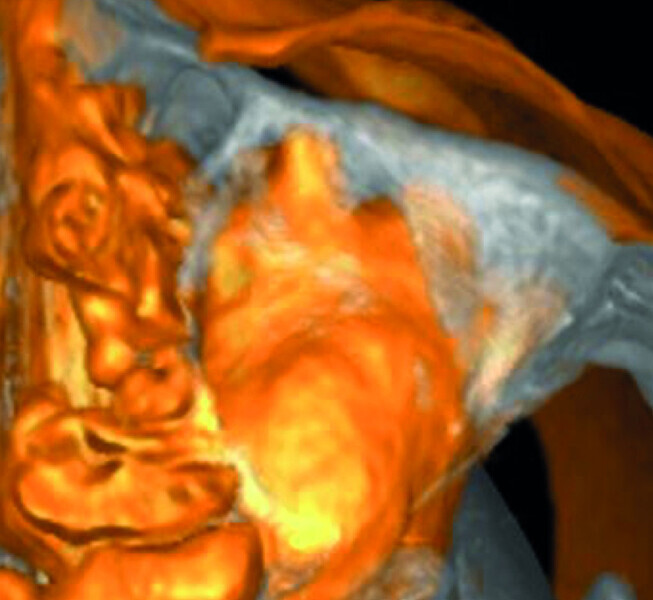

Maxillary sinus and root canal therapy complications